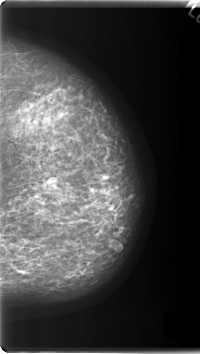

C_0213_1.LEFT_MLO

LEFT_MLO LINES 5928 PIXELS_PER_LINE 3648 BITS_PER_PIXEL 12 RESOLUTION 50 NON_OVERLAY